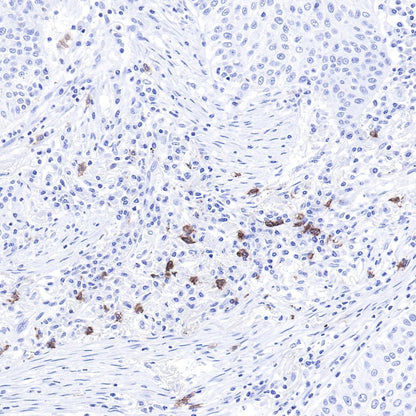

IHC shows positive staining in paraffin-embedded human lung cancer.

Anti-CD117 antibody was used at 1/1000 dilution, followed by a Goat Anti-Rabbit IgG H&L (HRP) ready to use.

Counterstained with hematoxylin.

Heat mediated antigen retrieval with Tris/EDTA buffer pH9.0 was performed before commencing with IHC staining protocol.